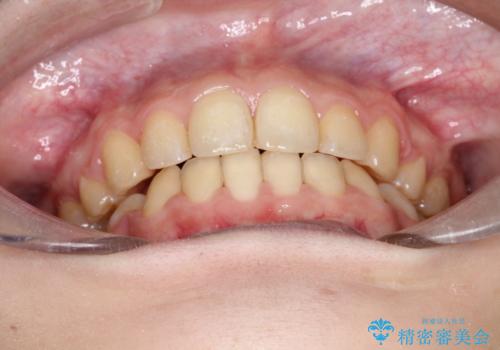

- 口元が出てるのが気になるとのことで来院されました。

歯のがたつきはあまりなかったのですが、口唇が閉じずらく、口元の突出感が確認できました。

上下左右の歯を1本ずつ抜歯して、そのスペースを利用して口元を引っ込める計画としました。